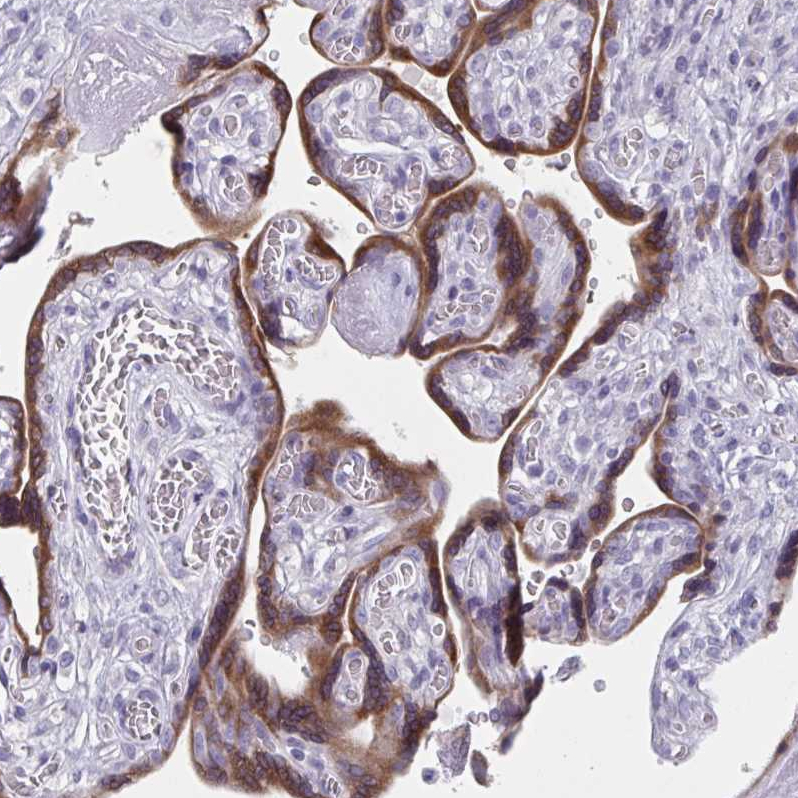

Immunohistochemistry analysis in human kidney and liver tissues using HPA042186 antibody. Corresponding HSD11B2 RNA-seq data are presented for the same tissues.